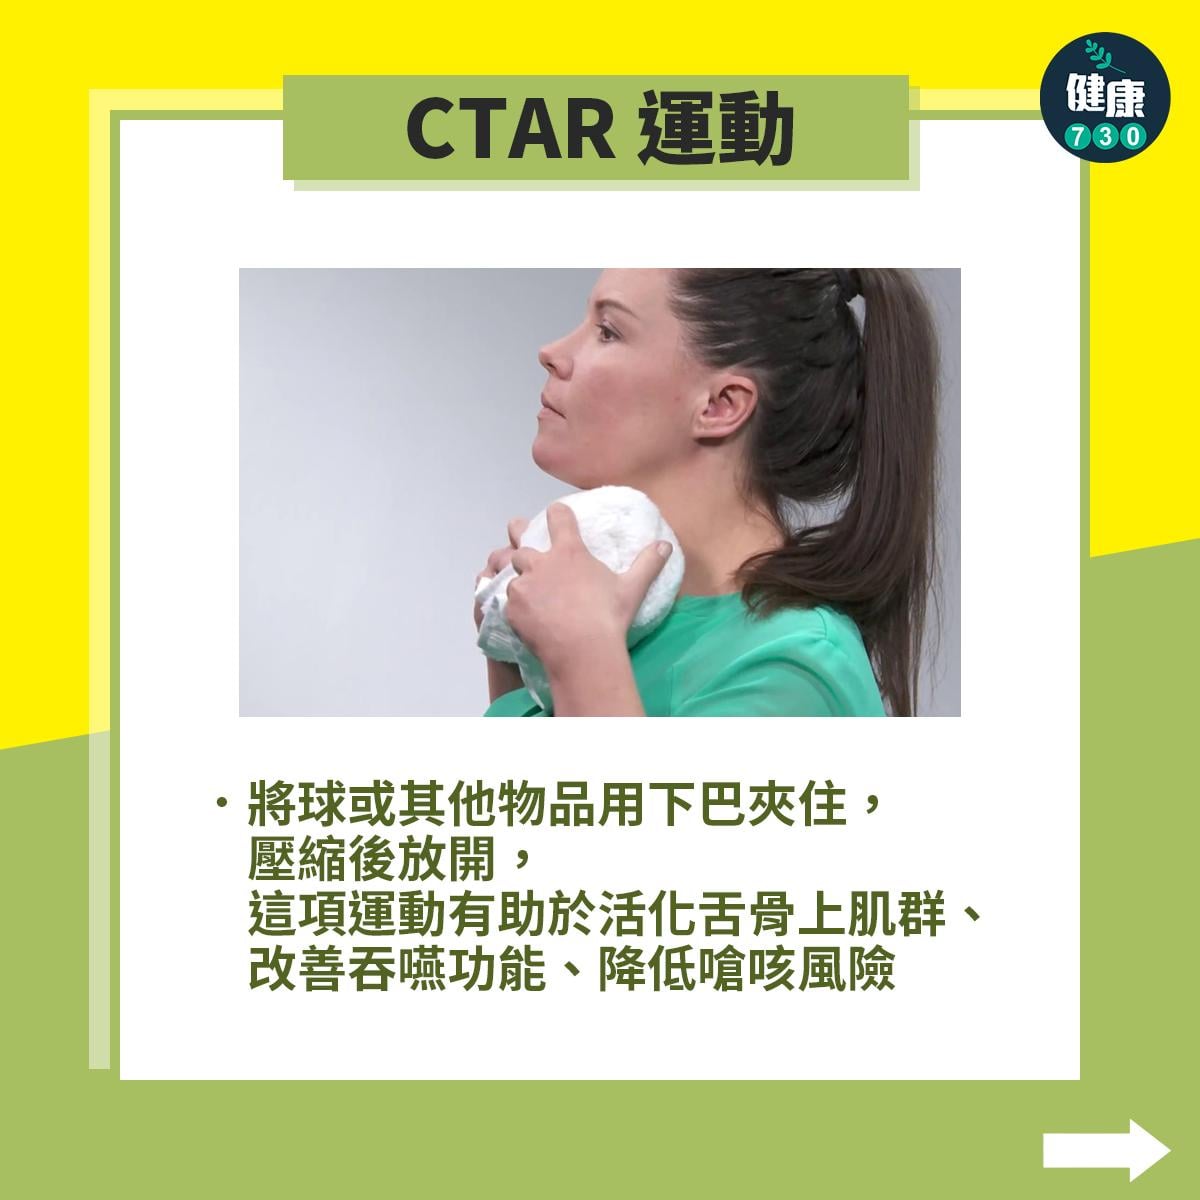

中風復健|5招改善中風後吞嚥困難